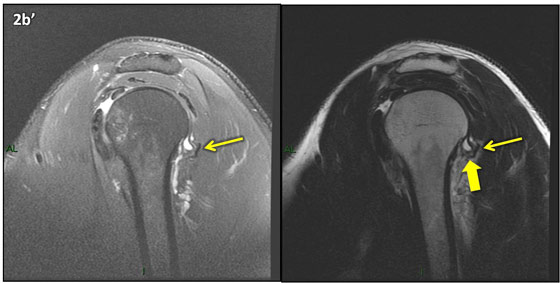

Figura 2 (a-j)': Imagens consecutivas de RM no plano sagital nas ponderaçõesT2 com supressão de gordura (DP SG) à esquerda e T2 à direita. Clique na seta para passar as imagens.

Figura 2a’ mostrando os tendões do subescapular (seta rosa), da cabeça longa do bíceps (seta verde), do supraespinhal (seta vermelha), do infraespinhal (seta laranja) e do redondo menor (seta amarela).

Figuras 2b a 2j’: Acompanhando o tendão do redondo menor (seta amarela fina) é possível notar lipossubstituição ao redor da junção miotendínea (setas amarelas grossas) e a atrofia principalmente da porção mais lateral (seta salmão). A porção mais medial (seta branca) tem volume preservado.

Repare que estas alterações também não são evidentes nas imagens com supressão de gordura no plano sagital.

Chafik et al. também relataram a presença de um pequeno nervo motor acessório em número variável que se insere na porção lateral do músculo redondo menor. O nervo acessório, ao contrário do principal, tem um curso reto e extra-fascial, sendo menos vulnerável aos efeitos compressivos. De fato, nos casos da atrofia parcial do redondo menor, é mais frequente a atrofia da porção mediodorsal com preservação da porção lateroventral, o que poderia ser explicada pela presença do ramo acessório mais lateral do nervo axilar, embora atrofia isolada do componente lateroventral tenha sido reportada em cerca de 17% dos casos de atrofia de apenas uma porção, o que pode ter sido causada por lesão do nervo acessório. No caso do paciente deste mês, a atrofia é mais evidente nesta porção mais lateral e ventral do redondo menor.

É importante que o protocolo de ressonância magnética do ombro tenha sequências ponderadas em T1, T2 ou densidade protônica (DP) sem supressão de gordura em pelo menos dois planos, idealmente nos planos coronal e sagital, para a detecção de lipossubstituição que pode passar despercebida nas imagens com supressão de gordura.